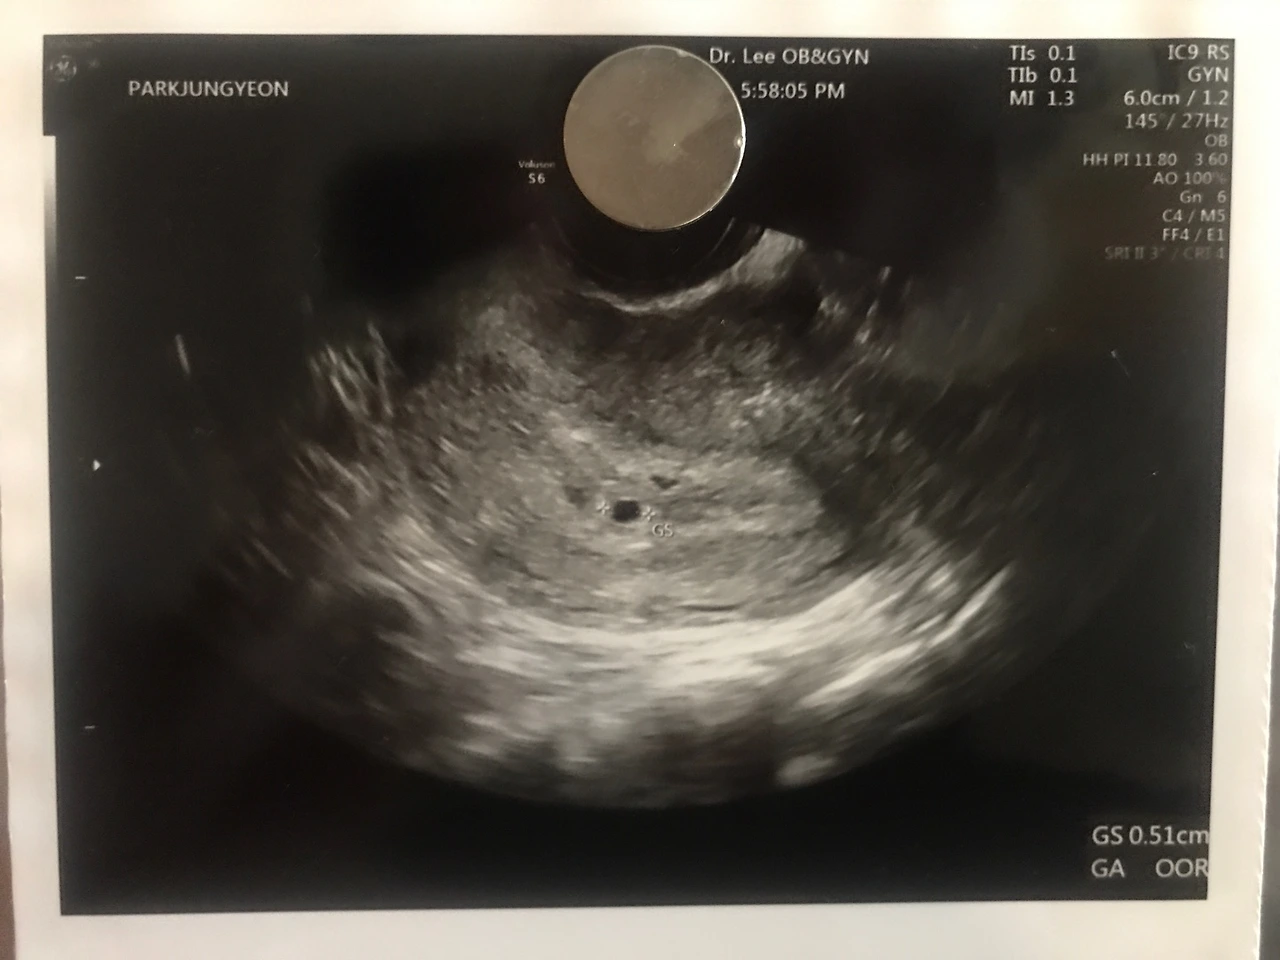

축하해 주세요! 여러분! 새로운 식구가 생겼습니다. 아들인지 딸인지 말랐는지 뚱뚱한지 키가큰기 작은지 똑똑한지 재주꾼인지 알 수는 없지만! 저 사진속 가운데에 있는 저 조그마한 녀석이 바로 피피의 새식구 '알콩이' 입니다.

알콩이는 현재 4-5주차로 뇌(Brain)를 만들고 있는 중이에요! 다음 주엔 아마도 심장과 위 등의 장기를 만들고 있을거에요. 1주일만에 사람의 형태를 띈다고 하니 정말 놀랍죠?